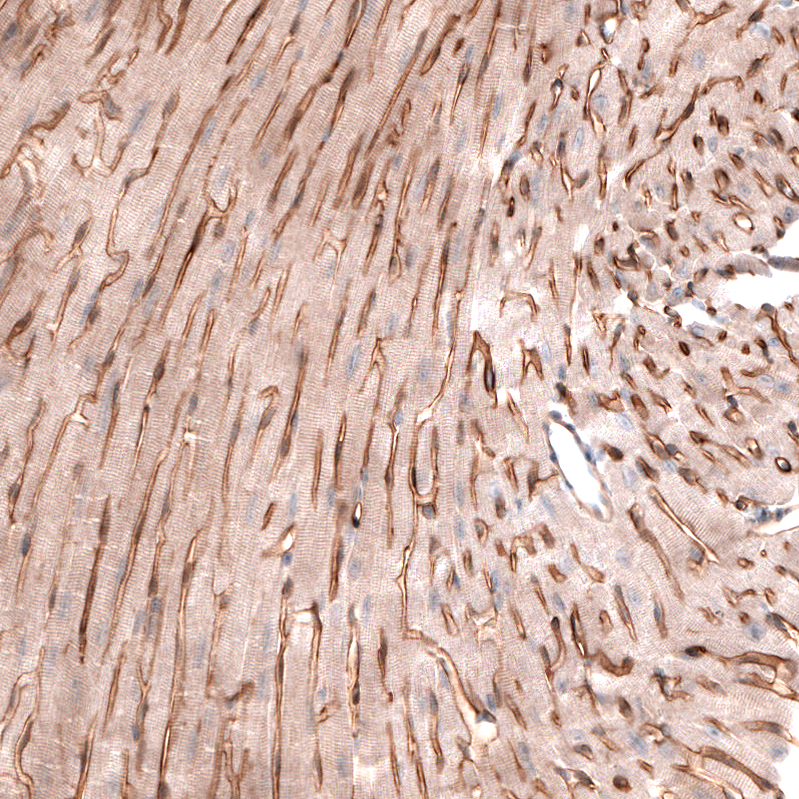

Staining of mouse heart muscle shows strong membranous positivity in cardiomyocytes.